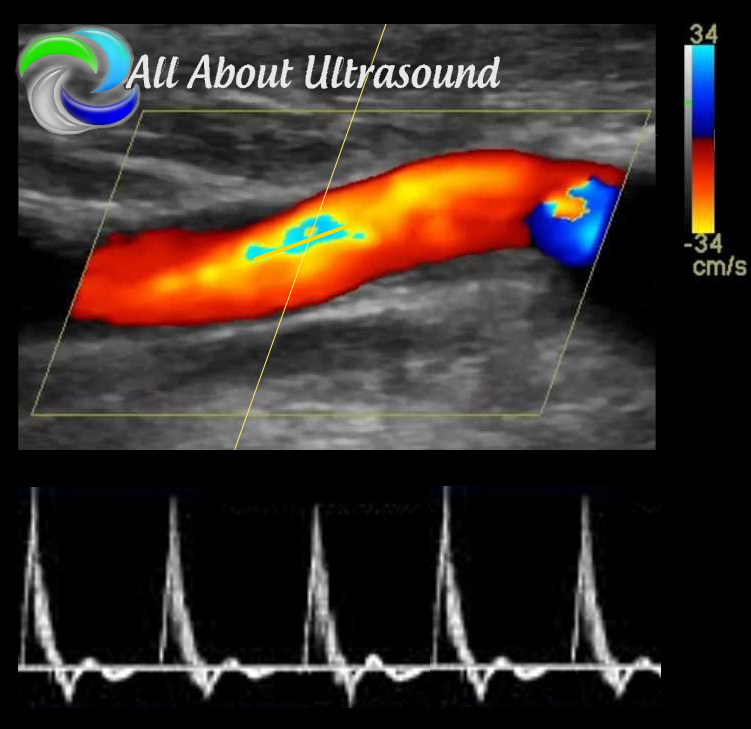

Vascular Ultrasound

Registry Review Quiz

Our Vascular Ultrasound Registry Review - Test & Learn Quiz can help you prepare for your vascular registry exam. No need to be intimidated. Our unlimited quiz has over 500 questions in the question bank and will help you learn as you go, testing your knowledge and teaching too! Our test responses are based on your answers and questions are designed to help you learn as you go with exam questions and answers, rotated and randomized with each 50 question quiz attempt. Pass your ARDMS® RVT registry exam or CCI® RVS registry exam. Become a registered vascular sonographer, study with us today!